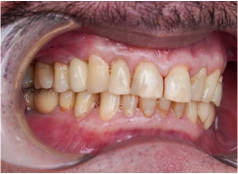

• Tình trạng răng trước đây:Mất nhiều răng, bị tiêu xương hàm

• Cấy ghép 6 trụ Implant loại Implant Mis C1 Đức

• Phục hình răng sứ loại răng sứ Titan Mỹ

Kết quả nhận được cũng đúng như mong muốn của chú. Trụ Implant tích hợp thành công vào xương hàm, sau 4 tháng đã có thể gắn răng sứ cố định và chú ăn uống thoải mái ngay sau đó. Từ ngày có hàm răng mới chắc khỏe, chú Hùng không còn phải chịu nỗi cám cảnh đau nhức mỗi khi ăn uống, nhờ đó tâm lý cũng thoải mái hơn rất nhiều.